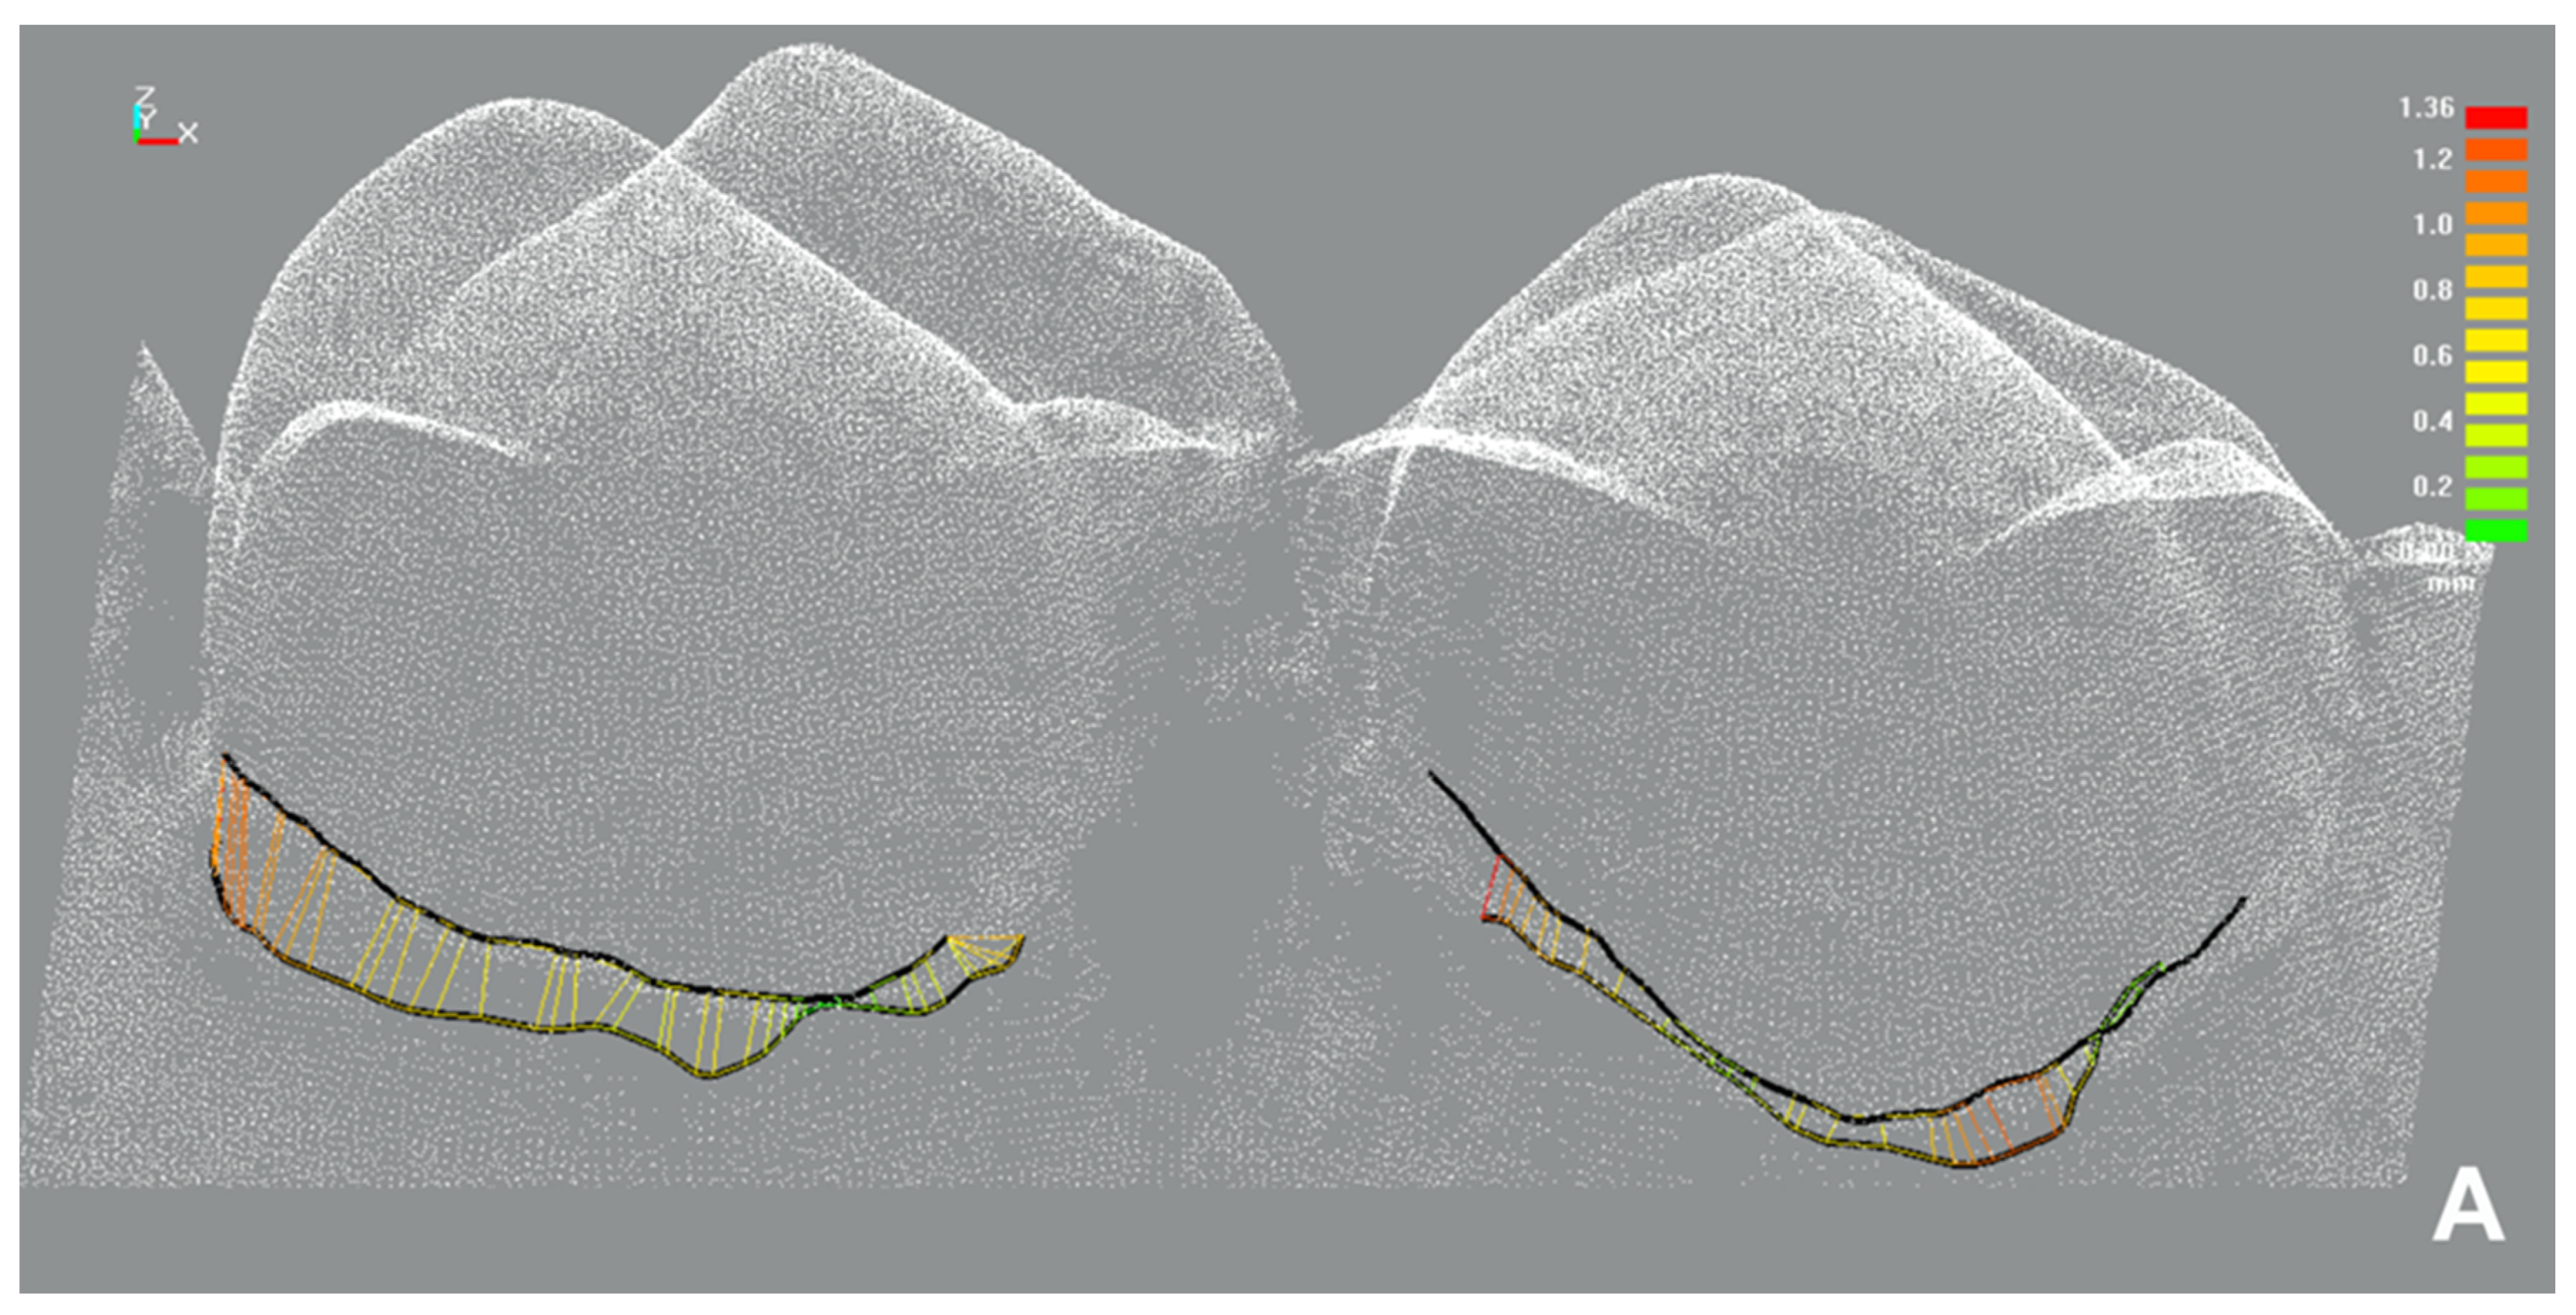

2.4.1. Sulcus Representation

3.5.1. Sulcus Representation (Primary Outcome), t-Test for Dependent Samples

Influence of an Intervention Performed

Influence of the Gingival Displacement Method

Influence of Gingival Condition

| Cord | −0.37 | −0.50 | −0.24 | −0.18 | −0.26 | −0.10 |

| Paste | −0.10 | −0.20 | −0.00 | −0.07 | −0.15 | 0.01 |